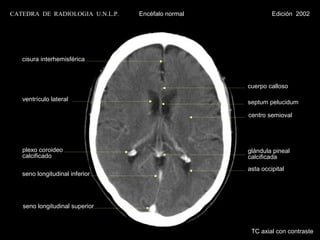

CATEDRA DE RADIOLOGIA U.N.L.P.   Encéfalo normal            Edición 2002

cisura interhemisférica

cuerpo calloso

ventrículo lateral                              septum pelucidum

centro semioval

plexo coroideo                                  glándula pineal

calcificado                                     calcificada

asta occipital

seno longitudinal inferior

seno longitudinal superior

TC axial con contraste